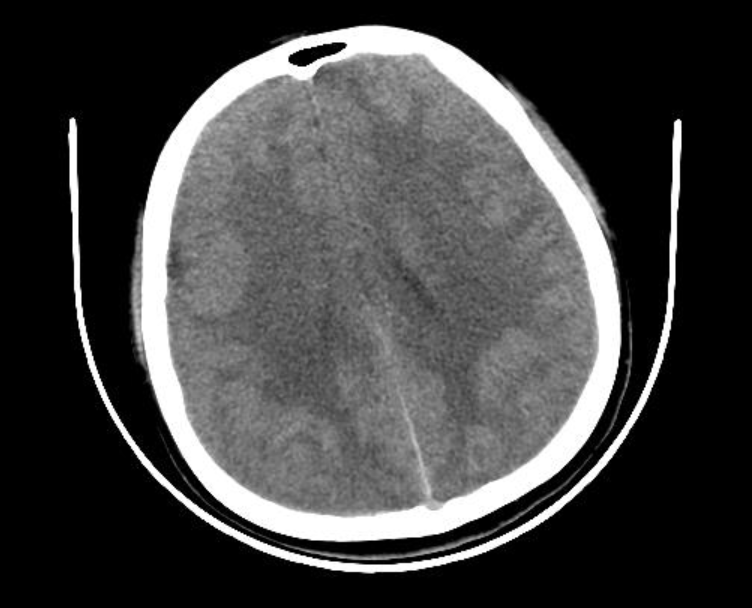

脑部ct

请帮我看下这份ct片,脑病主要病变在哪里,有什么治疗方式